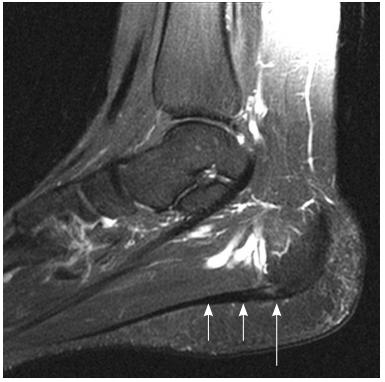

如果查磁共振(尽管一般不会),会在片子上看到下面的景象,也就是足底筋膜在脚后跟区域有明显的炎症水肿。